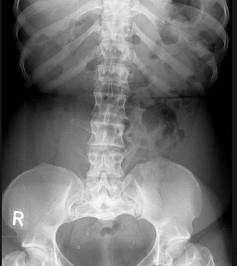

女,41岁,身材矮小,背痛,请结合图像,选出最可能的诊断 ( )A、石骨症B、马方综合征C、腰椎间盘突出D、软骨发育不全E、腰椎退行性变

问题 女,41岁,身材矮小,背痛,请结合图像,选出最可能的诊断 ( )

选项 A、石骨症 B、马方综合征 C、腰椎间盘突出 D、软骨发育不全 E、腰椎退行性变

答案 D